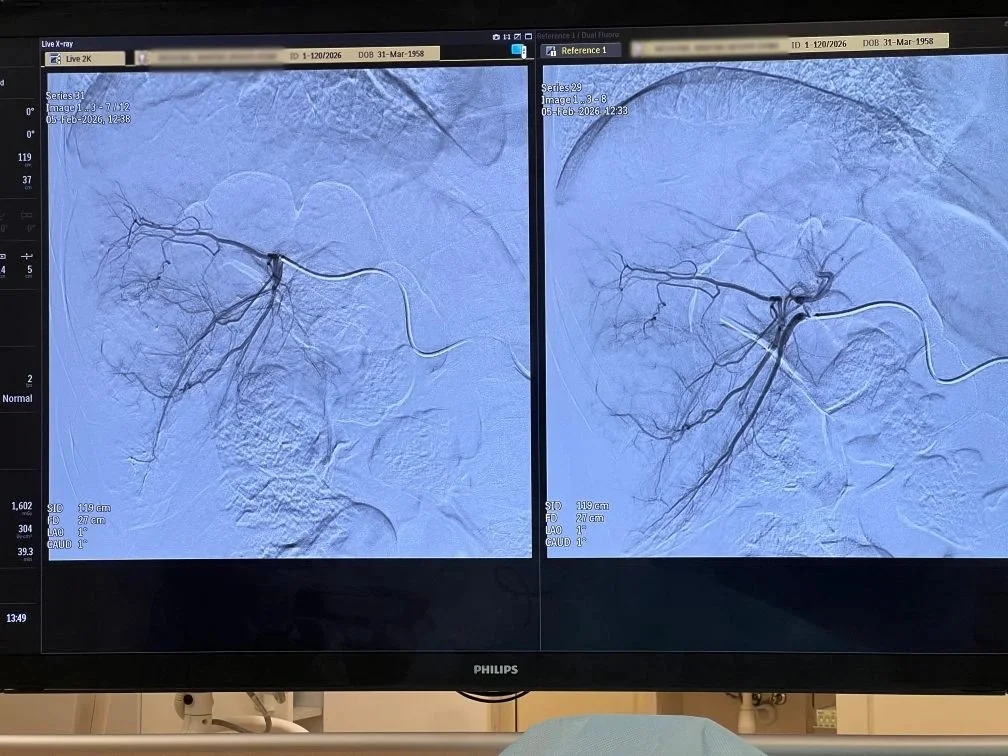

В итоге метастатические очаги у пациентки были пролечены сначала методом химиоэмболизации: медики точечно доставили в опухоль концентрированный химиопрепарат и перекрыли питающие ее артерии. После чего подвергли еще два метастаза радиочастотной абляции.

Радиочастотная абляция – это современный метод лечения, при котором через прокол в опухолевый узел вводится игла-электрод. Под действием высокочастотного тока его ткани нагреваются, и опухоль разрушается. По своей эффективности способ не уступает хирургической резекции.

Вся операция продлилась более трех часов. Подведение электрода к очагу выполнялось под двойным контролем: с использованием рентген-диагностики сосудов, вен и артерий, а также УЗИ. Это особенно важно, поскольку вблизи опухолей проходят важные сосуды и структуры, которые такой подход позволяет сохранить.